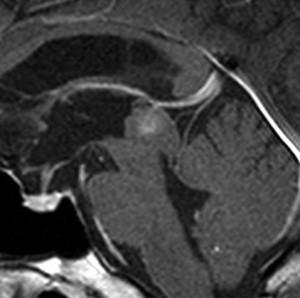

15歳時に水頭症で発症して増大しなかった例

この例が画像としては典型的な中脳視蓋グリオーマと言えます。手術摘出できないタイプです。

15歳の時に頭痛と嘔吐,視力と視野障害がでました。閉塞性水頭症だったので第3脳室開窓術を受けました。この時の診断は松果体腫瘍でした。でも翌年,開窓部が詰まってしまって,V-Pシャント(脳室腹腔短絡術)を受けました。でもシャントが詰まってしまって,頭痛と嘔吐と意識障害(昏睡、除脳硬直)を生じる急性シャント不全になり,シャント手術のやり直しをしました。21歳の時にもシャント不全で意識障害になり,シャント手術のやり直しをしました。その3ヶ月後にもまたシャント不全でシャント再建術を受けて,それから私の外来に来ました。

左はT1強調画像,右はFLAIR画像です。中脳視蓋が腫れて腫瘍がにじむように広がっているのがわかります。この腫瘍本体は15歳の時から21歳の時まで大きくなっていないので,中脳視蓋グリオーマ tectal gliomaの診断です。

T1強調ガドリニウム増強画像です。15歳の時は腫瘍の半分以上が強くガドリニウム増強されていましたが,この21歳の時の画像では,中心部やや右寄りに増強像が認められるだけです。この性質は,腫瘍が毛様細胞性星細胞腫であることを示しています。